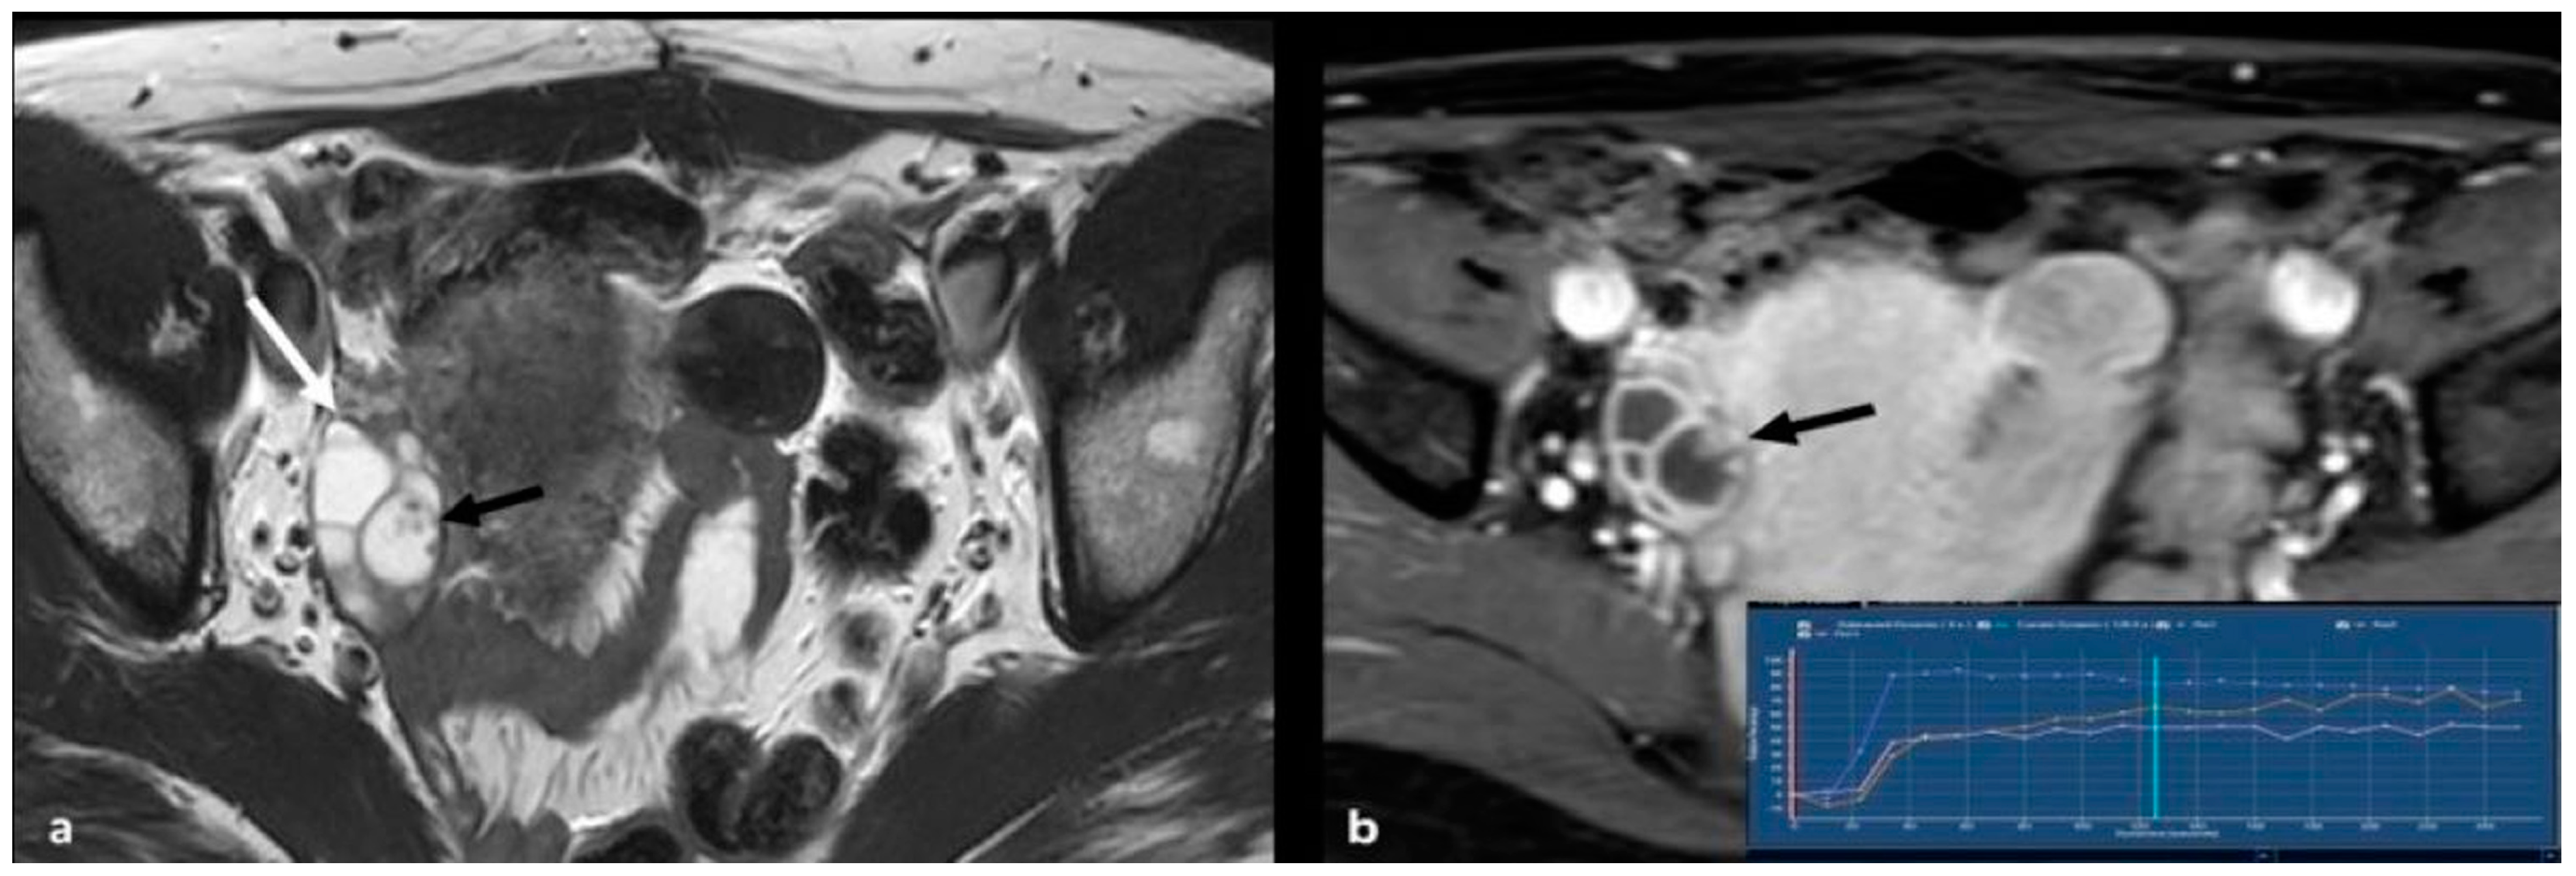

2.3.4. Lymphoma

2.3.5. Metastases